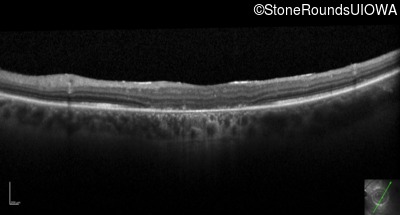

Optical Coherence Tomography - Right - 10/125 +1 sc

Exemplar / OCT Stack